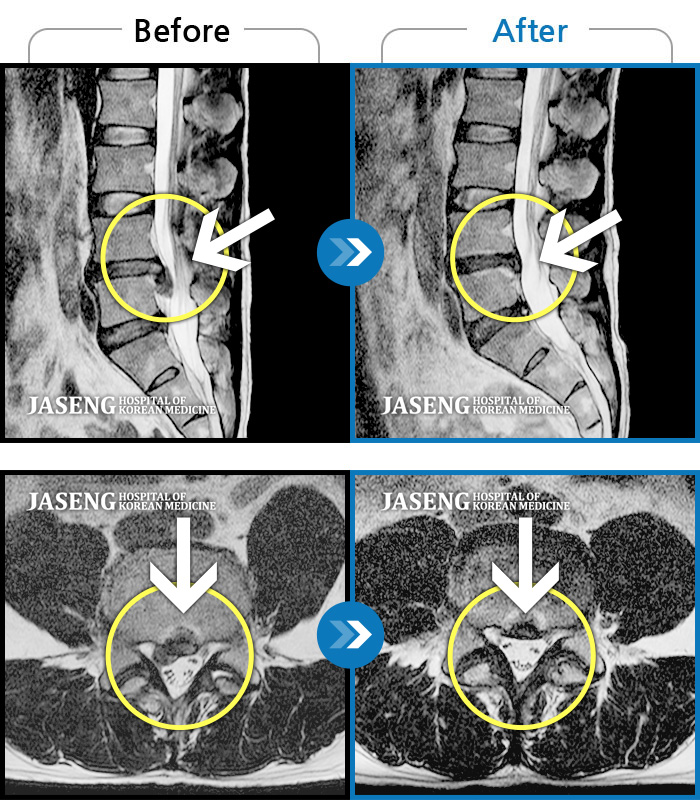

허리디스크

인천 · 강아현 원장

물건을 들다 삐끗한 후 발생한 허리 통증 및 하지 방사통, 하지 감각 저하 및 근력 저하 발생

촬영시기

2025.03.04 ~ 2025.09.10

2025.09.22

조회수 248